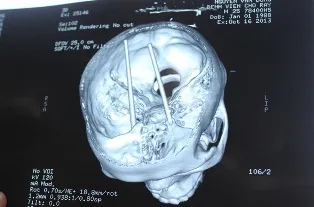

Hình ảnh từ kết quả chụp CT cho thấy 2 chiếc đũa đã xuyên ngập hoàn toàn trong não - Ảnh: My Lăng

Ngay chiều đó, BV Đa khoa Bà Rịa đã chuyển bệnh nhân lên BV Chợ Rẫy để cấp cứu. Phim chụp CT cho thấy toàn bộ 2 chiếc đũa dài khoảng 18cm đã cắm ngập xuyên từ hốc mắt qua sàn sọ, xuyên vào thân não.